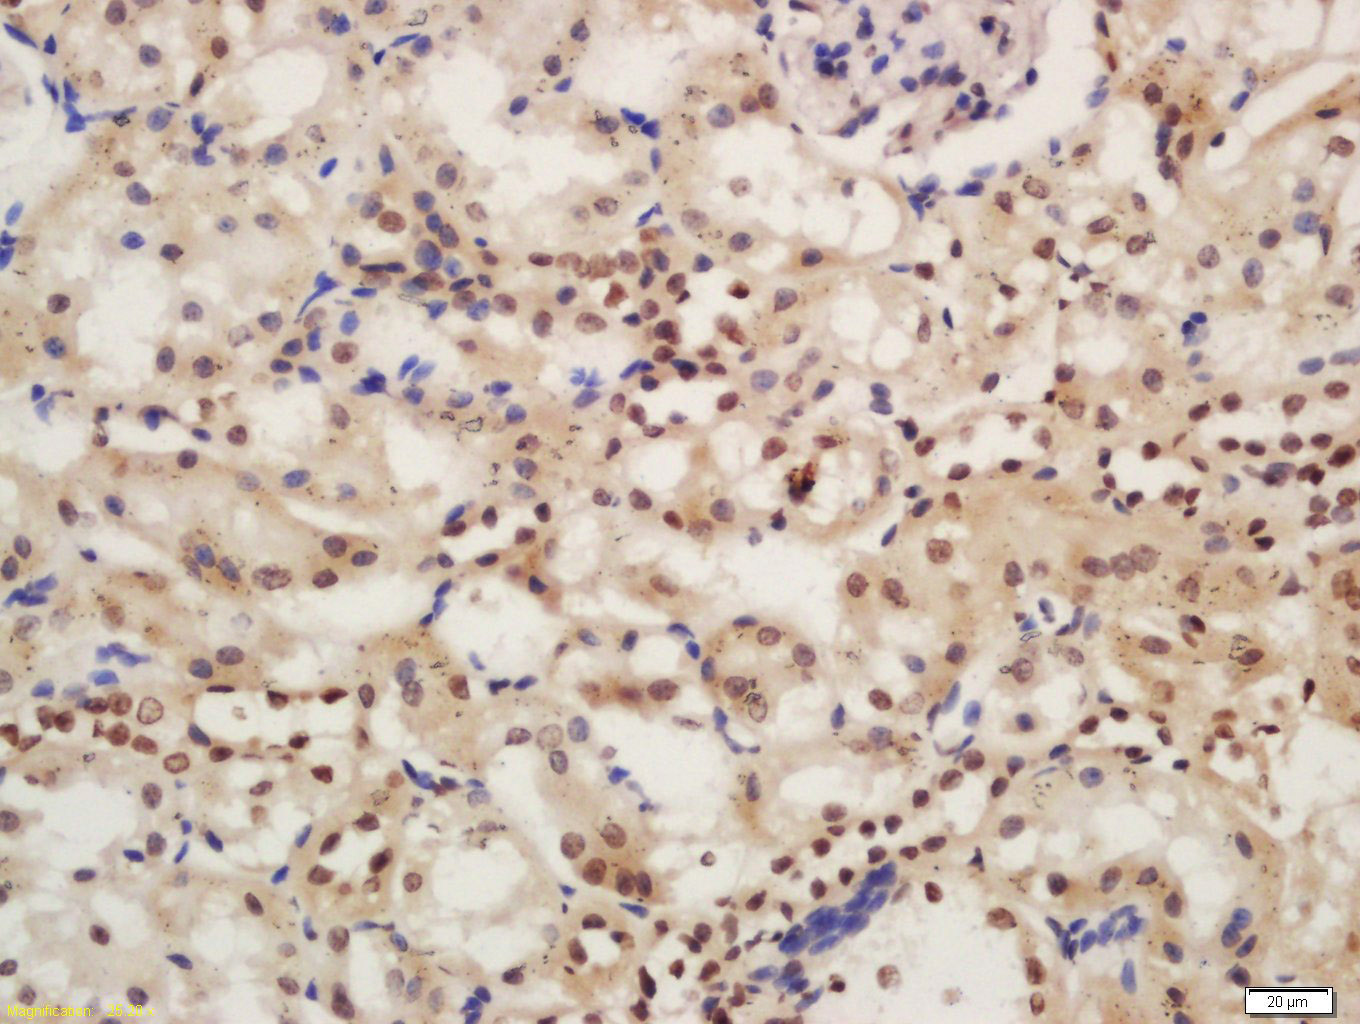

phospho-IRAK1 (Ser376) Rabbit pAb

| IHC-P, IHC-F, IF |

| Immunogen | KLH conjugated Synthesised phosphopeptide derived from human IRAK1 around the phosphorylation site of Ser376 |

| Epitope Specificity | QS(p-S)TV |

| Dilution | IHC-P=1:100-500,IHC-F=1:100-500,ICC/IF=1:100-500,IF=1:100-500,Flow-Cyt=1ug/test |